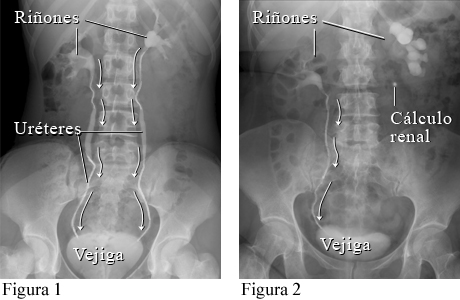

Cálculo renal visto en una pielografía intravenosa (IVP)